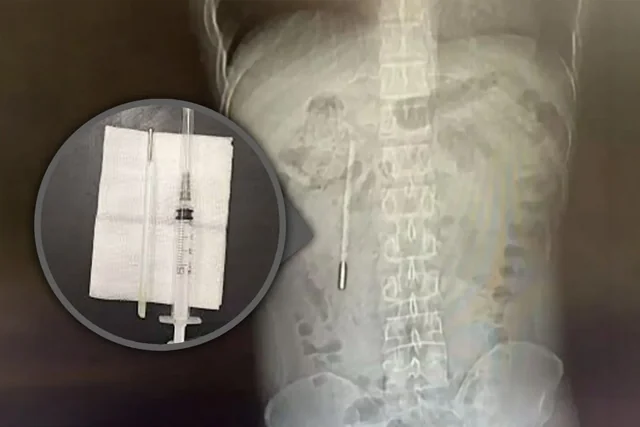

Həkimlər müayinə zamanı pasiyentin onikibarmaq bağırsağında yad cisim - 20 il əvvəl udulmuş civəli termometr aşkar ediblər. Məlum olub ki, cihazın ucu birbaşa bağırsaq divarına təzyiq etdiyi üçün perforasiya (deşilmə) və güclü daxili qanaxma riski yaranıb.

Zərərçəkən bildirib ki, 12 yaşında olarkən termometri təsadüfən udub, lakin valideynlərinin danlayacağından qorxduğu üçün bu barədə heç kimə məlumat verməyib. /Oxu.az/